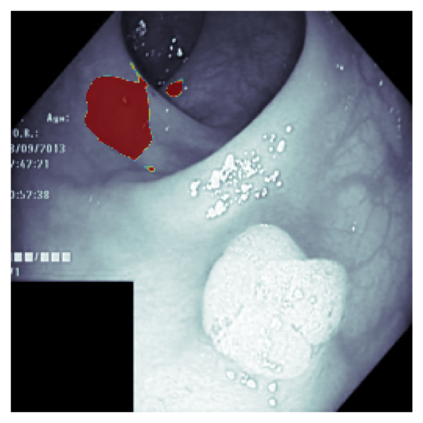

The sigmoid activation is the standard output activation function in binary classification and segmentation with neural networks. Still, there exist a variety of other potential output activation functions, which may lead to improved results in medical image segmentation. In this work, we consider how the asymptotic behavior of different output activation and loss functions affects the prediction probabilities and the corresponding segmentation errors. For cross entropy, we show that a faster rate of change of the activation function correlates with better predictions, while a slower rate of change can improve the calibration of probabilities. For dice loss, we found that the arctangent activation function is superior to the sigmoid function. Furthermore, we provide a test space for arbitrary output activation functions in the area of medical image segmentation. We tested seven activation functions in combination with three loss functions on four different medical image segmentation tasks to provide a classification of which function is best suited in this application scenario.